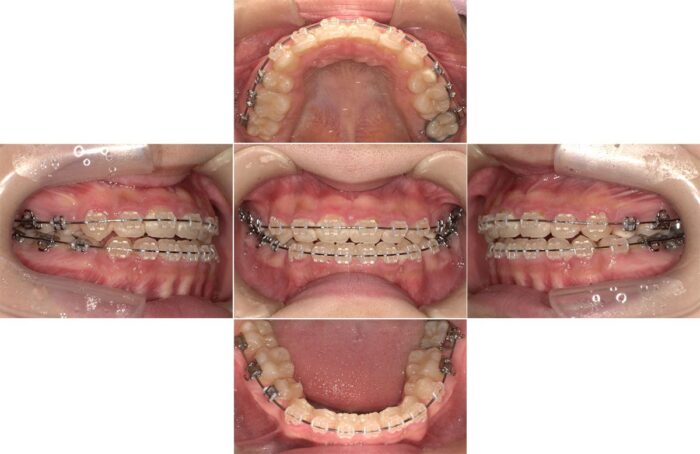

出っ歯とすきっ歯の改善を希望されて相談にいらした患者さまです。口元の突出感が気になるとのことだったので、抜歯矯正をお勧めしましたが、患者さまのご希望で歯を抜かずに治療を開始しました。

治療を始めてから半年が経過したころ、患者さまからご相談があり治療方法を変更することになりました。

やっぱり口元が気になるので歯を抜きたいです

先ほどご紹介したように、ガタガタのない歯列の歯を抜く場合、隙間を閉じるための歯の移動距離が長く、マウスピース単独だと治療に時間がかかる症例です。

隙間が閉じるまでワイヤー矯正で進め、隙間が閉じたらマウスピースに戻ってかみ合わせを調整する方針で治療を再スタートしました。

矯正治療で歯を抜くか抜かないか迷っている方へ、歯を抜く決心がついた時は早めに教えてくださいね!

歯を抜いたことで横顔の変化が大きく、気にされていた口元の突出が解消されました。

食事(特に給食)のたびにマウスピースを外すことが負担だったそうで、結局マウスピースに変更せず、最後までワイヤーで治療を行いました。

- 使用装置:マウスピース矯正装置(インビザライン)、表側ワイヤー矯正

- 治療期間:2年10ヶ月